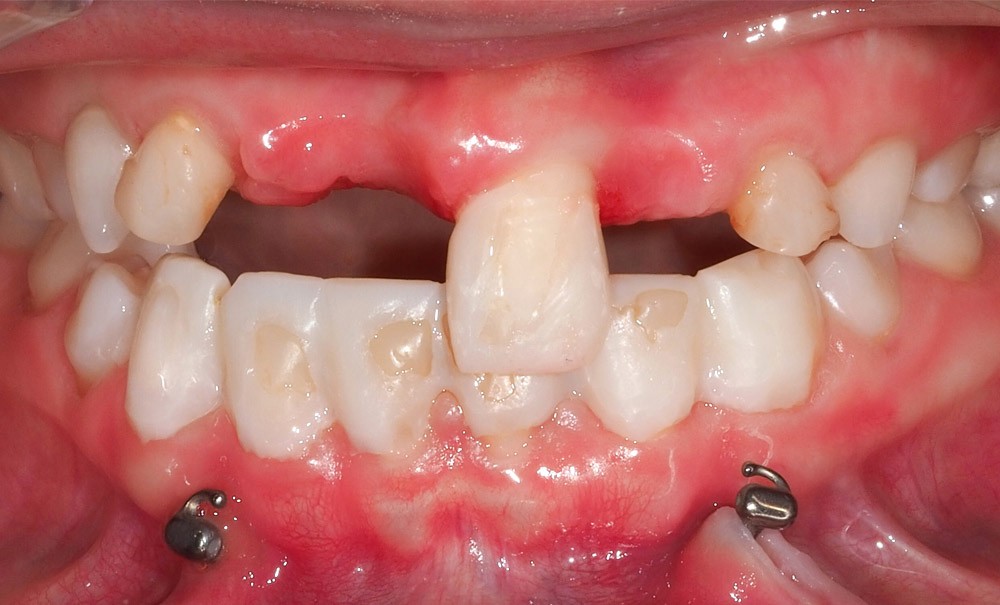

À l’examen clinique et radiographique, nous constatons que, malgré son âge, le patient présente toujours une denture mixte. On retrouve seulement 5 dents permanentes sur l’ensemble des deux arcades. Les autres dents toujours en place dans la cavité buccale sont des dents temporaires, qui ne se sont pas exfoliées à cause de l’absence des dents successionnelles(fig. 1, 2). L’incisive centrale maxillaire permanente gauche (dent 21) présente une anomalie de forme, avec une morphologie coronaire conoïde. De plus, l’espace inter-canin maxillaire est anormalement large, laissant de l’espace pour placer six incisives. Les dents antérieures maxillaires et mandibulaires présentent des restaurations adhésives directes, dont les joints de collage sont infiltrés, afin de modifier leurs morphologies.